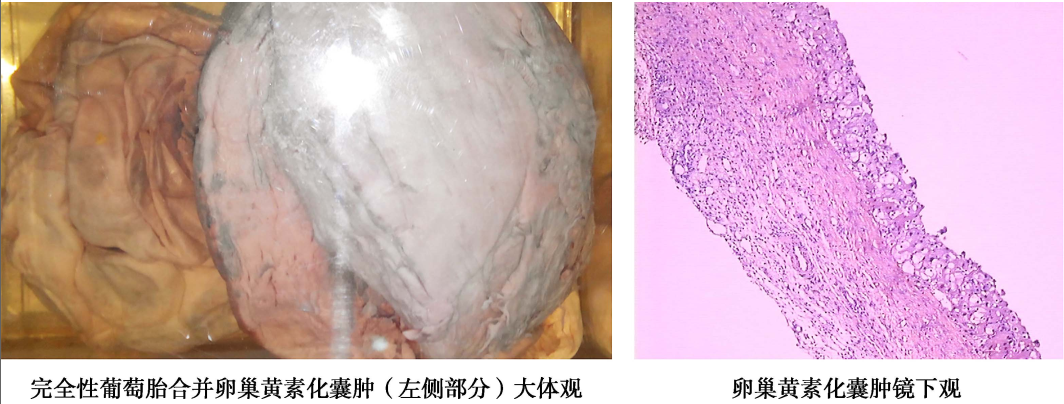

(7)卵巢黄素化囊肿(theca lutein ovarian cyst):大量hCG刺激卵巢卵泡内膜细胞发生黄素化而造成,常为双侧,但也可单側,大小不等,最小仅在光镜下可见,最大可在直径20cm以上。囊肿表面光滑,活动度好,切面为多房,囊壁薄,囊液清亮或琥珀色。光镜下见囊壁为内衬2~3层黄素化卵泡膜细胞。黄素化囊肿一般无症状。由于子宫异常增大,在葡萄胎排空前一般较难通过妇科检查发现,多由超声检查作出诊断。黄素化囊肿常在葡萄胎清宫后2~4个月自行消退。

卵巢黄素化囊肿大体观和镜下观(100×)